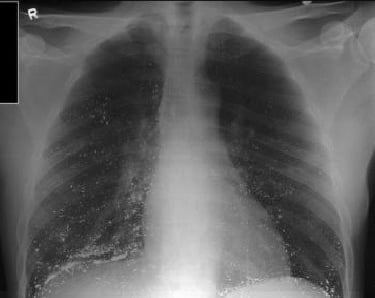

Yüksek düzeylerde cıva maruziyeti sonrası, ölümlerin primer nedeni akciğer hasarıdır (pulmoner ödem).